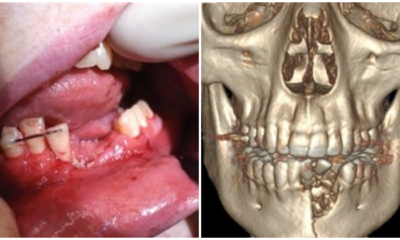

With e-cigarettes and vapes becoming more and more popular now, it’s terrifying to know that such an incident actually happened to someone. A vape pen exploded...